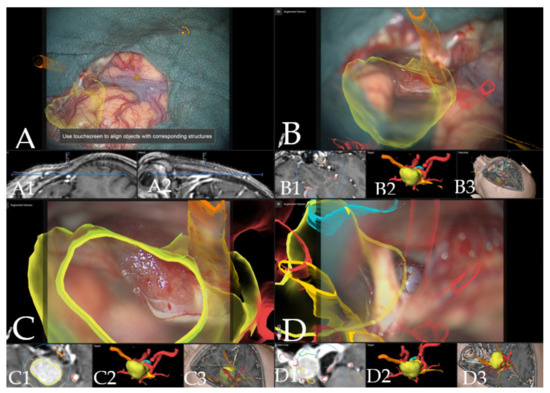

Case 3: A 67-year-old female patient (patient number 19) with visual deterioration and bitemporal hemianopsia. MRI showed a suprasellar meningioma which was resected via right pterional approach. Figure 7 demonstrates the visualization of the structures in the AR throughout the surgery.

Figure 7. Navigation and augmented reality support during surgery (patient no. 19, same patient as in Figure 1). (A) Three-dimensional visualization of the segmented objects as seen through the microscope video with head up display (tumor in yellow, optic chiasm and optic nerves in orange), showing navigation update after craniotomy with focus on Sylvian fissure in (A1) axial and (A2) coronal view of the standard navigation. (B) Three-dimensional visualization of segmented objects (with vessels in red) following retraction of the frontal lobe with (B1) corresponding probe’s eye view, (B2) target view and (B3) overview depicting the video plane in relation to the segmented objects in 3D fashion. (C) Microscope video of tumor exposure with head-up display with (C1) corresponding probe’s eye view, (C2) target view and (C3) overview of the video plane. (D) AR display on video screen with the 3D outline of tumor, carotid arteries, optic nerves and chiasm with focus on the carotid artery, following complete resection of the tumor with (D1) probe’s eye view, (D2) target view and (D3) overview of the video plane.